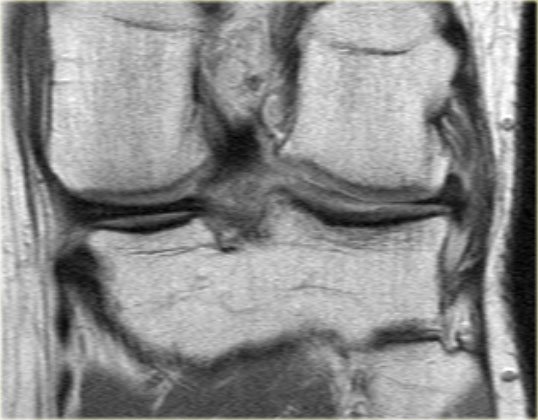

Hình bên trái là một sụn chêm khác với tăng tín hiệu lan tỏa tại thân sụn chêm.

Trên các lát cắt khác (không hiển thị) không có bằng chứng của rách sụn chêm.

Lưu ý tình trạng thoát vị sụn chêm nặng vượt ra ngoài bờ mâm chày.

- Dấu hiệu sụn chêm trong sụn chêm và thoát vị phần giữa sụn chêm (mũi tên đỏ).

- Rách xuyên tâm hoàn toàn tại sừng sau.

Lưu ý thêm hình ảnh hoại tử vô mạch. - Lưu ý thêm hình ảnh hoại tử vô mạch.

- Thoát vị sụn chêm kèm hoại tử vô mạch.